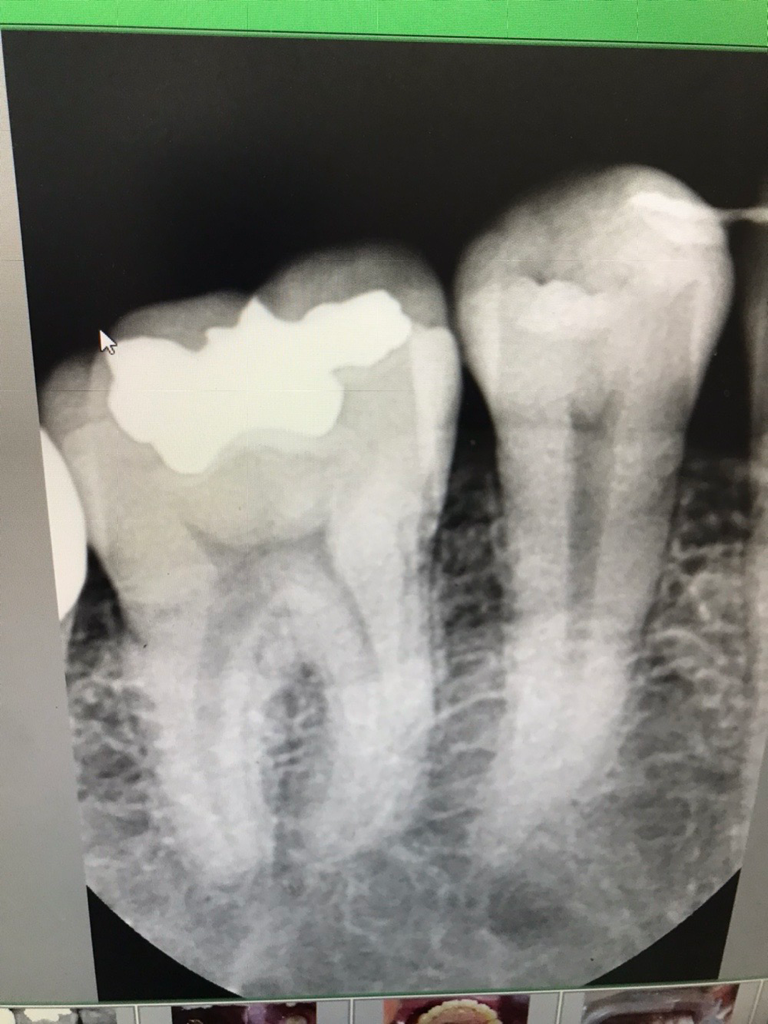

엑스레이 상으로는 크게 문제가 없어 보입니다. 아마 잇몸관리가 안되서 염증이 생긴거 같습니다.

차진불은 크게 문제가 없어 보입니다. 하지만 치아 주변에 염증이 있다면 이런 염증은 사진에 나타나지 않기 때문에 잇몸에 염증이 있다면 잇몸 치료를 받아주는 거죠 좋습니다. 자세한 확인을 위해서 치과에서 진료를 받아보는 것을 권유드립니다.

사진에 특별하게 나타나는 문제는 보이지 않습니다. 잇몸이 아프고 부으면 잇몸 염증의 문제일 가능성이 있습니다.

해당 사진만으로는 말씀하신 부분에 대해 정확히 알 수 없습니다. 사진은 2차원적이며 임상 검사 등을 같이 해보아야 합니다. 지속적으로 잇몸 및 치아 통증이 있다면 치과 방문 후 해당 치아에 대한 다각도적인 검사를 해보셔야 합니다.